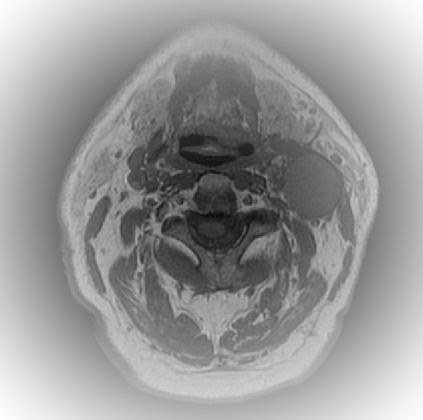

Organ at risk (OAR) segmentation is a critical process in radiotherapy treatment planning such as head and neck tumors. Nevertheless, in clinical practice, radiation oncologists predominantly perform OAR segmentations manually on CT scans. This manual process is highly time-consuming and expensive, limiting the number of patients who can receive timely radiotherapy. Additionally, CT scans offer lower soft-tissue contrast compared to MRI. Despite MRI providing superior soft-tissue visualization, its time-consuming nature makes it infeasible for real-time treatment planning. To address these challenges, we propose a method called SegReg, which utilizes Elastic Symmetric Normalization for registering MRI to perform OAR segmentation. SegReg outperforms the CT-only baseline by 16.78% in mDSC and 18.77% in mIoU, showing that it effectively combines the geometric accuracy of CT with the superior soft-tissue contrast of MRI, making accurate automated OAR segmentation for clinical practice become possible. See project website https://steve-zeyu-zhang.github.io/SegReg